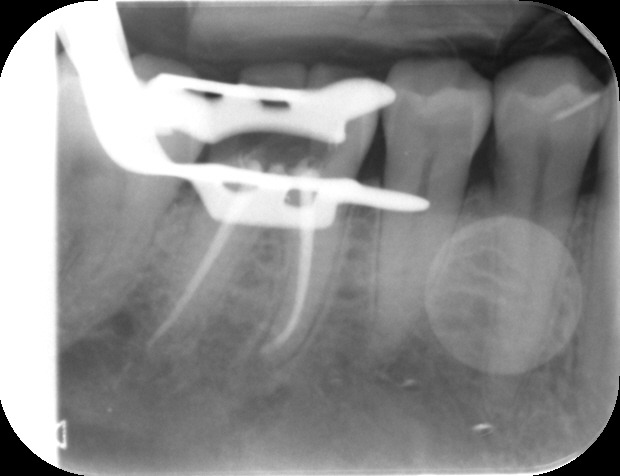

Before commencing the treatment, a local anaesthetic is administered and later a protective non-latex rubber sheet is placed around the tooth to prevent saliva contaminating the tooth and at the same time improves patients comfort.

An access cavity is placed on the surface where the patient bites, to reach the root canals of the tooth. Once all the canals are identified, small files are used to remove the infected pulp.

Files of different sizes are used to eliminate bacteria and infection and to shape the canals. The canals are disinfected thoroughly with irrigants and later the canals will be sealed in 3 dimensions with a special medicament called gutta-percha to prevent reinfection of the tooth and the access cavity will be sealed with a temporary filling.